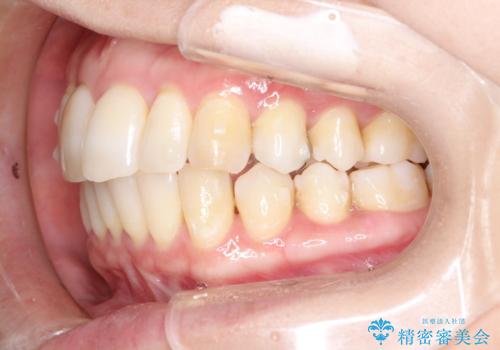

再矯正をインビザラインで目立たず手軽に

- 以前矯正をしていたが、わずかに後戻りをしてしまったのを主訴に来院されました。

装置はなるべくつけたくないとのことで、インビザラインにて治療することとなりました。

以前ワイヤー矯正をされていた方は、装置をつけての再矯正を希望されない方もいます。

その場合にインビザラインをお勧めさせていただいております。

後戻りがわずかな場合は、期間も短くて済む場合があります。